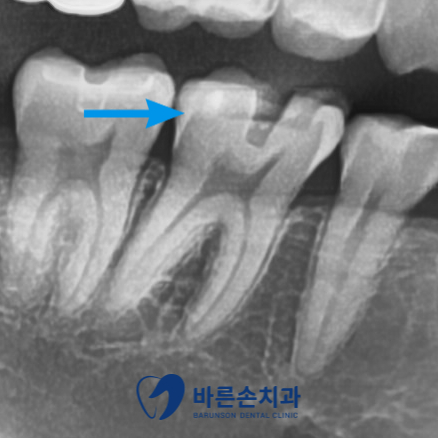

사진에서 보시면

★ 오른쪽 위 두번째 큰 어금니는 인접면 우식이 심하게 진행 -> 신경치료와 크라운